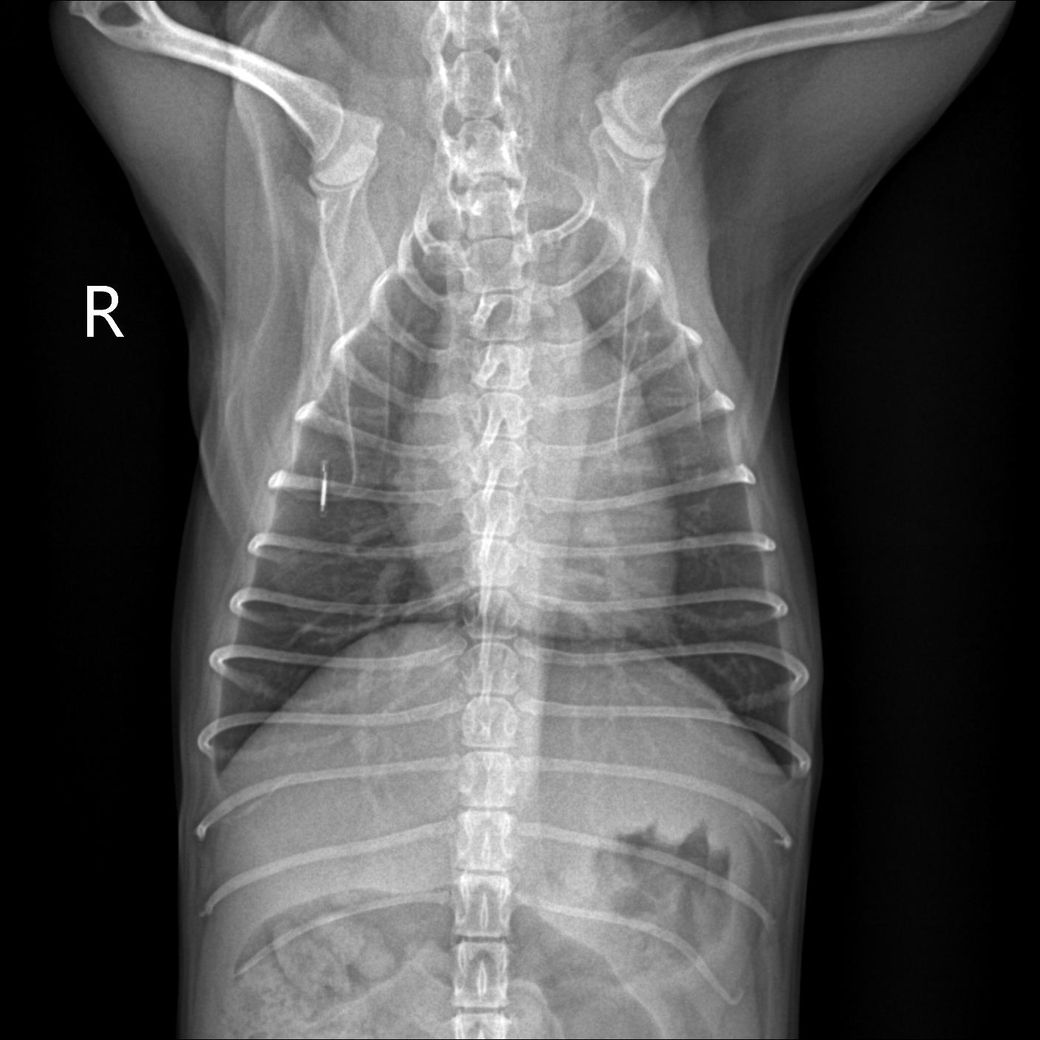

경추 4-5-6번의 추간판 사이가 좁아보이며 동시에 복부 방사선 촬영 시 결장에 가스가 많이 차 있는 것을 볼 수 있습니다.